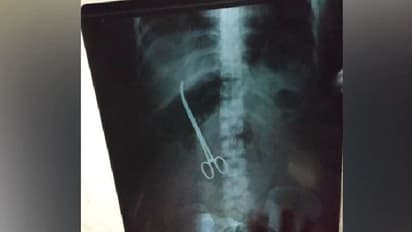

ആശുപത്രിയിൽ എത്തി എക്സ്റേ എടുത്തപ്പോഴാണ് ശസ്ത്രക്രിയയ്ക്ക് ഉപയോഗിക്കുന്ന കത്രിക വയറ്റിൽ കുടുങ്ങിയത് കണ്ടെത്തിയത്. തുടർന്ന് ശനിയാഴ്ച രാവിലെ അടിയന്തര ശസ്ത്രക്രിയ നടത്തി ഉപകരണം നീക്കം ചെയ്യുകയായിരുന്നു. ആദ്യ ശസ്ത്രക്രിയ നടന്ന് മൂന്നു മാസത്തിന് ശേഷമാണ് യുവതിയുടെ വയറ്റിൽ നിന്നും കത്രിക പുറത്തെടുക്കുന്നത്. അതേസമയം തങ്ങൾ രോഗികൾക്കാണ് മുൻതൂക്കം നൽകുന്നതെന്നും അതുകൊണ്ടാണ് പിഴവ് മനസ്സിലാക്കി ഉടൻ ഉപകരണം നീക്കം ചെയ്തതെന്നും നിംസ് ആശുപത്രി ഡയറക്ടർ കെ മനോഹർ പറഞ്ഞു.